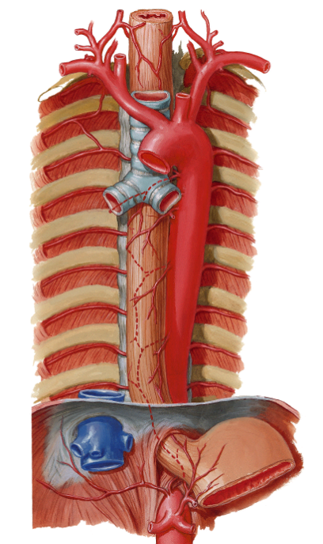

- Blood supply to the rib cage originates from what 2 places?

- what 2 arteries supply the intercostal spaces of the rib cage

- what branch off of the subclavian artery goes down specifically to the diaphragm?

aorta and subclavian artery

Anterior and posterior intercostal arteries

notice how branches from the aorta go around and supply the rib cage

the internal thoracic artery

look at picture

study picture

the 3rd through the 11th intercostal arteries branch off from what?

notice it in the picture?

from the aorta

Posterior intercostal arteries:

- There are only 11 “posterior intercostal arteries” that supply what?

- The ________ which arises from aorta helps supply what as it runs inferior to the rib?

the 11 intercostal spaces

subcostal artery

the 12th rib

notice how in the picture you can see the subcostal artery down below the ribs as it branches from the aorta

Anterior intercostal arteries:

- These arteries branch from where?

- then this originates from where?

internal thoracic artery

- Internal thoracic artery originates from subclavian artery

the internal thoracic artery comes from the ____________ vein and then runs behind the anterior ________?

subclavian vein

anterior sternum

notice the internal thoracic artery coming down right near the sternum

The Anterior intercostal arteries supply which intercostal spaces?

- The lower intercostal spaces supplied by what?

1-9

posterior intercostal arteries

notice how the intercostal arteries run superior and inferior in the intercostal spaces

look at all the arteries and their relationship

look at how the posterior intercostal arteries come from the back and wrap around the intercostal spaces from the back

look at picture